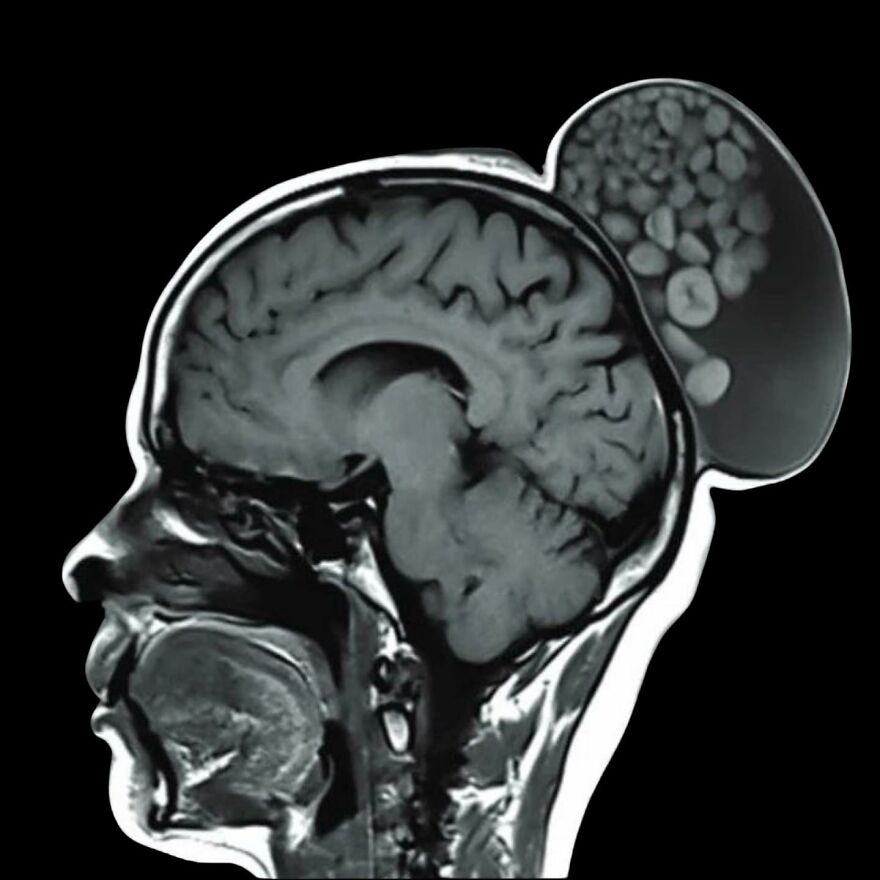

In an unusual surgery, doctors in Bengaluru removed a bulging growth from a woman's head that resembled a "sack of marbles."

The medical term for these globules is dermoid cysts. They are essentially tissue spheres that form from embryonic cells and may contain "hair, teeth, or nerves."

These globules can appear anywhere on the body, including one's ovaries and various areas of the head and neck.

Dermoid cysts are often harmless, but they don't resolve on their own and need to be removed surgically.